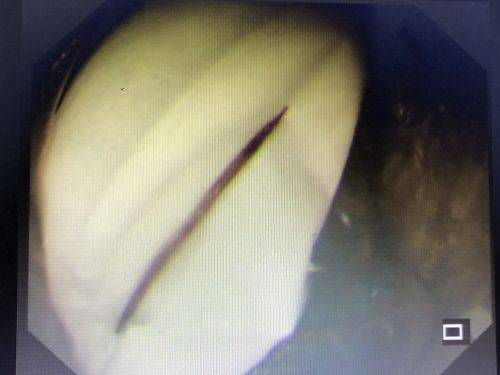

影像资料上可以看到胃里的异物(鼠标所示)。

牙签已经将胃壁戳了2个洞。